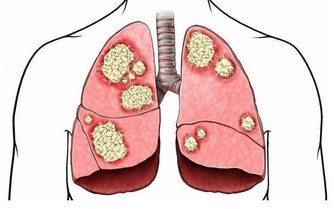

它可以保護您的細胞免受損害和感染,並保持甲狀腺正常運轉。硒還可以保持肌肉強壯,並可以幫助預防與年齡相關的疾病,例如癡呆,某些類型的癌症和甲狀腺疾病。每天只吃一兩個巴西堅果就足夠了。不要過多,因為硒過多會使頭髮掉落並使指甲變脆。

維生素B9的這種天然形式存在於綠葉蔬菜,堅果,豆類和其他食品中。孕婦採用實驗室製造的稱為葉酸的維生素B9,以幫助預防嬰兒出生缺陷。葉酸有助於細胞生長,並可以預防中風和某些癌症了。食物中的葉酸是安全的。但是,補品或強化食品中的葉酸過多會增加患結腸癌或神經損傷的機率。